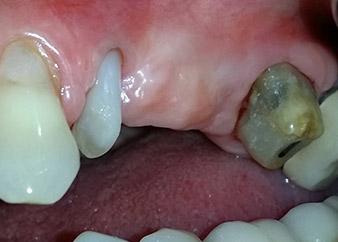

One month later, on the day of surgery, pain and inflammation at tooth 24 were minimal, but mobility of Miller class 2 was still present. After opening the flaps and cleaning the periapical and peri radicular infected tissue, the extent of the bone defect became obvious (Figs. 2 and 3).

At the buccal root, all vestibular and distal bone was missing. Attachment was essentially restricted to the palatal root, underlining the preliminary poor prognosis. Tooth 27 also showed a reduced horizontal attachment and a minimal apical rarefaction (cf. Fig. 1) without clinical symptoms.